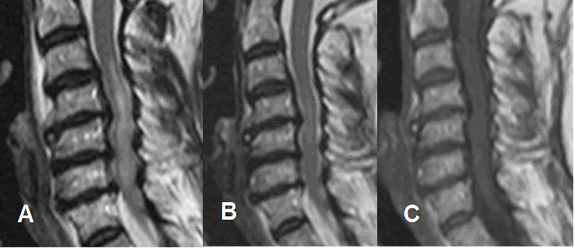

Fig 180 A. Lesión medular mixta.

A: RM sagital en T2 y B: RM sagital en STIR. Paciente con canal estrecho y trauma en hiperflexión. Se aprecia la medula engrosada e hiperintensa entre C3 y C6, por edema.

C: RM sagital en GE. En la zona central hay area lineal, hiperintensa en T2 e hipointensa en GE, sugestivas de sangrado.

Fig 180 B. Lesión medular. Igual paciente anterior.

A: RM sagital en T2. Medula engrosada y con zonas hiperintensas, por edema. Hay canal estrecho asociado.

B: RM sagital en T2 y C: RM sagital en T1. Control posterior, donde se aprecia disminución de los cambios inflamatorios. En T1 no hay áreas hiperintensas, con lo que se descarta la contusión hemorrágica.